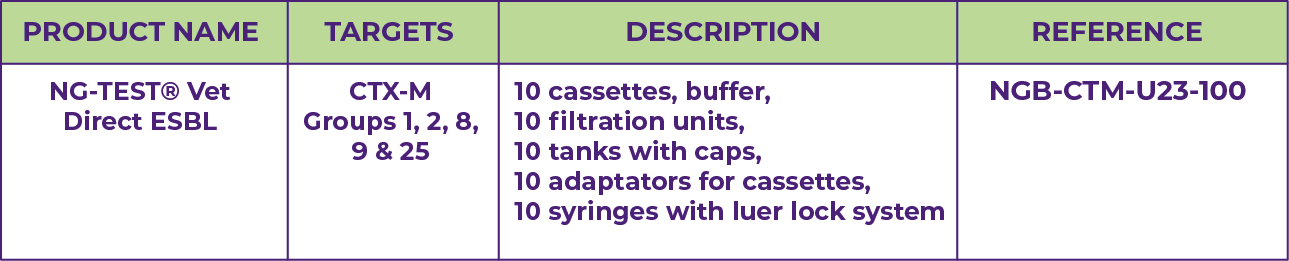

NG-TEST® Vet Direct ESBL

NG-TEST® Vet are easy-to-use and allows to have results in 15 min bacteria sample without any instrument.

NG-TEST® Vet Direct ESBL is a ready-to-use kit comprising a sample preparation device (DirecTool) and a rapid test in cassette format (CTX-M Multi) designed for the detection of the main extended-spectrum β-lactamase (ESBLs).

PRINCIPLE

The NG-TEST® Vet is a rapid immunoassay for the detection of groups 1, 2, 8, 9 and 25 CTX-M β-lactamases in Enterobacterales extracted irectly from urine sample.